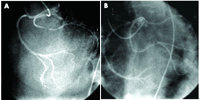

一例42岁男性在非ST段抬高心肌梗死后接受了冠脉造影检查。该患者有早发冠心病家族史以及20多年大量吸烟史(3~4包/天)。检查结果提示左前降支(LAD)、回旋支和右冠状动脉(RCA)从同一出口发出(图A)。这三支冠脉均存在病变,LAD在第一对角支发出后完全闭塞,回旋支中段90%狭窄,RCA近段80%狭窄(图B)。[Heart 2007,93(9):1014]